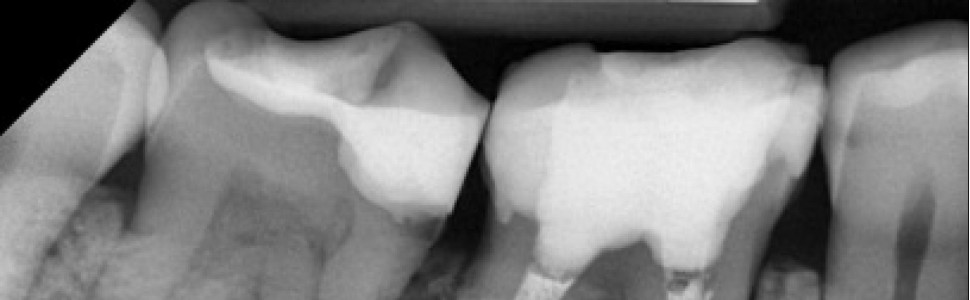

Lasery diodowe o długości fali 810 nm znajdują szerokie zastosowanie w stomatologii. Dzięki swoim właściwościom są chętnie wykorzystywane w leczeniu endodontycznym. Umożliwiają one skuteczniejszą dezynfekcję kanałów oraz delty korzeniowej, nawet zębów z rozległymi zmianami okołowierzchołkowymi. Ponadto lasery te działają przeciwbólowo, przeciwzapalnie i stymulująco na leczone tkanki okołowierzchołkowe. W pracy opisano dwa przypadki leczenia endodontycznego z wykorzystaniem lasera o długości fali 810 nm.